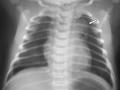

Intubação seletiva em recém-nascido

Dez de 2015.

16.089